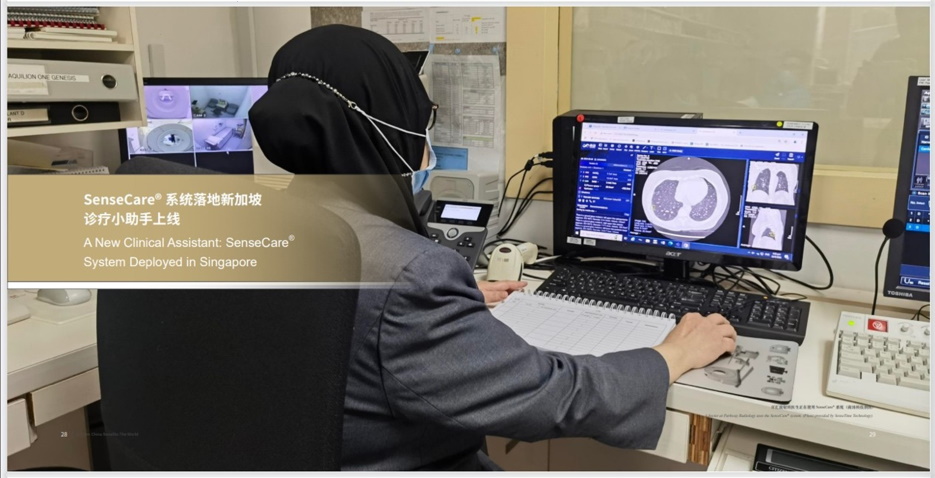

智能精準 AI成為可靠的臨床助手

面對東南亞的肺癌發病率不斷上升,SenseCare在臨床應用中,尤其是在肺結節等早期篩查與管理方面,展現出重要價值。作為醫生的「AI助手」,該系統可在短時間內精準識別CT影像中僅幾毫米大小的肺結節,並智能提示其潛在風險,有效提升篩查效率、降低漏診率。

SenseCare系統在IHH醫療(集團)百匯放射科全面落地後,已迅速融入醫生的日常診療流程,成為放射科的「標配工具」。百匯放射科每月進行上千例肺結節覆診,該系統替代了大量重複、繁瑣的人手比對工作,並提供自動化影像分析與量化數據支持,讓醫生能更專注於複雜的病情判斷,釋放醫務人員的寶貴時間,而患者亦能更快獲取檢查結果,享受更具前瞻性的健康管理及治療。此舉不僅推動醫院管理效能顯著提升,也促進了患者、醫生與醫療機構的多方共贏。

作為亞洲規模最大、醫療標準最高規格的私立醫療集團,IHH醫療(集團)對技術合作夥伴的准入條件極為苛刻。商湯醫療憑藉其在人工智能領域的領先實力與前瞻佈局,贏得了新加坡IHH醫療(集團)旗下的百匯放射科的高度認可。2024年,商湯SenseCare胸部CT智能分析系統在百匯放射科正式上線,成為區域內首個全面部署AI肺部篩查方案的私立醫療體系。

2024年,百匯放射科於新加坡網絡全面採用SenseCare胸部CT智能分析系統,體現了雙方共同致力運用AI,提供更智能、更高效且以患者為本的醫療服務。